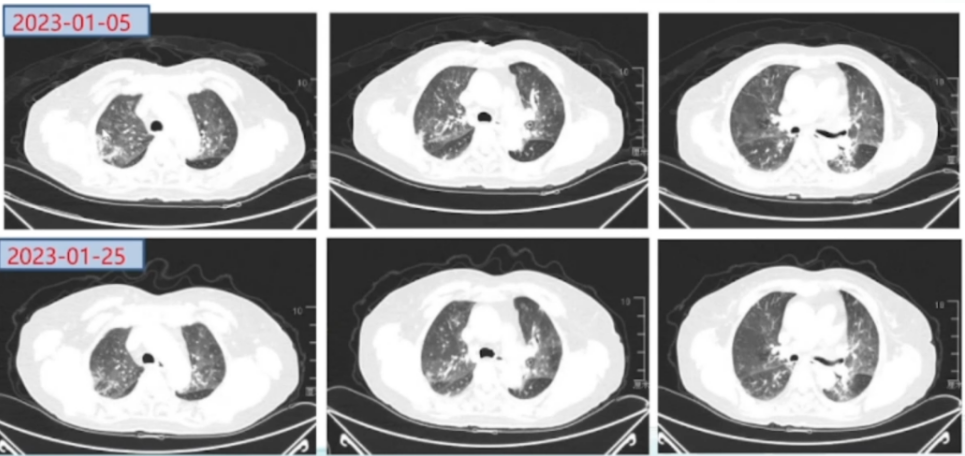

调整治疗1周后(2023-01-04)复查床旁胸片:两肺渗出较前有所吸收(图4)。复查胸部CT(2023-01-05): 两肺的磨玻璃影和渗出影较外院片显著吸收, 病变范围明显缩小(图5)

图片

5  治疗前后胸部CT对比